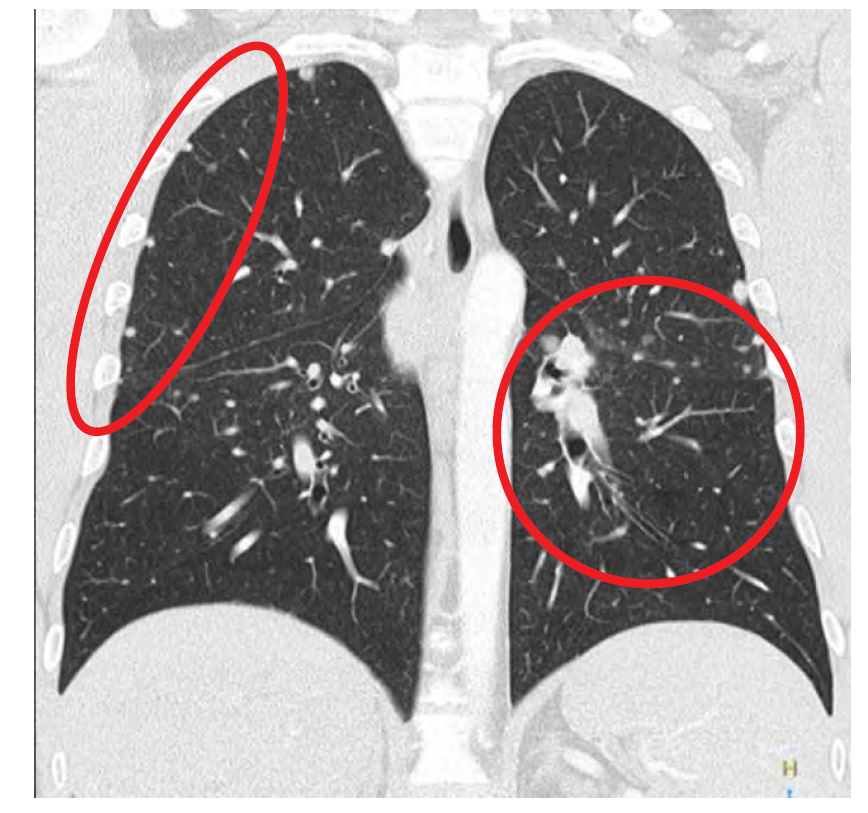

What do you see? What condition would this be?

Calcifications in lymph nodes and lymphadenopathy. Sarcoidosis.

What is this?

Sarcoidosis